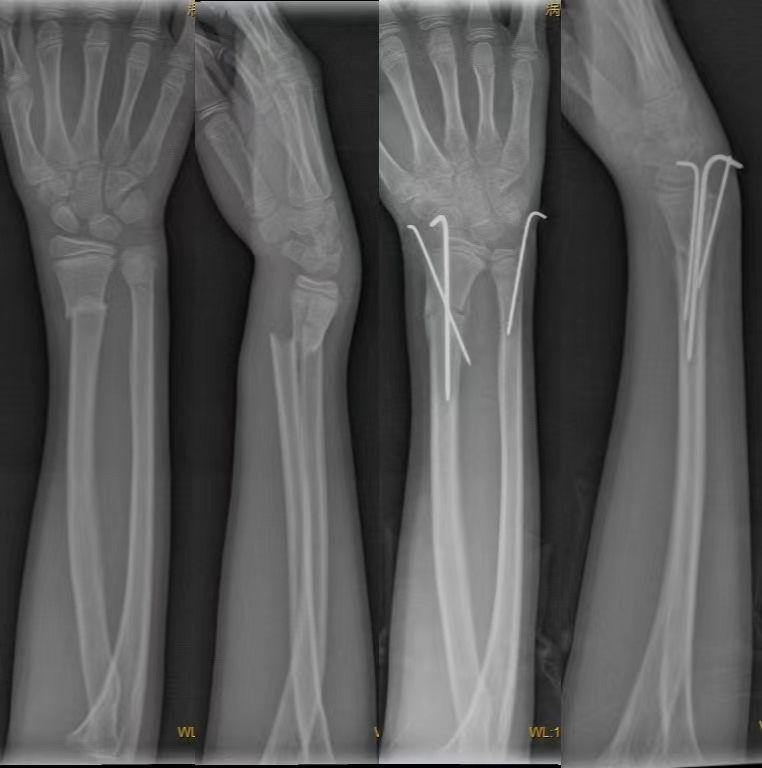

2.经皮穿针固定:具有手术简单、取出容易、较少影响肌腱功能等特点。适应征:既可以作为一种单独的外固定方法,也可以作为石膏外固定和外固定架的有效辅助措施。单独应用时,适用于关节外骨折,闭合复位后早期出现再移位的骨折,以及一些能闭合复位但无法靠外固定维持位置的关节内骨折。年龄<65岁的关节外骨折、伴有干骺端轻微粉碎的骨折或无移位的关节内骨折。